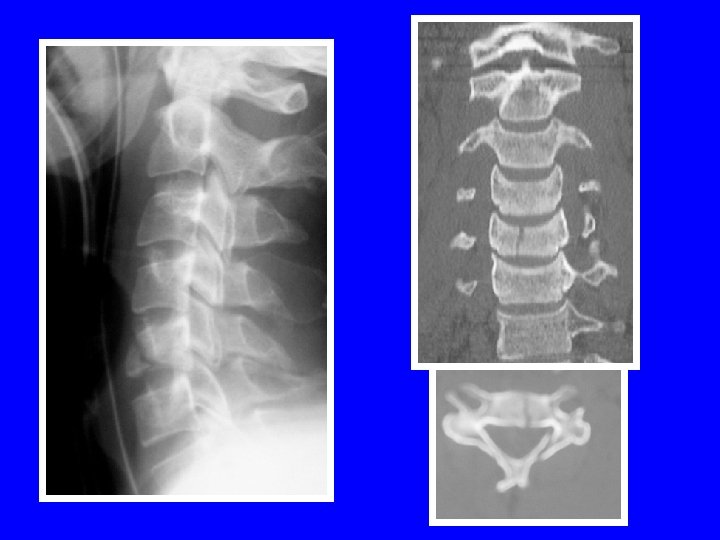

LUXATION PURE BILATERALE 41% de lésions médullaires pointes à pointes accrochage bilatéral

LUXATION UNILATERALE

24% atteintes médullaires 68% atteintes radiculaires

FRACTURE SEPARATION D ’UN MASSIF ARTICULAIRE Retentissement foraminal++